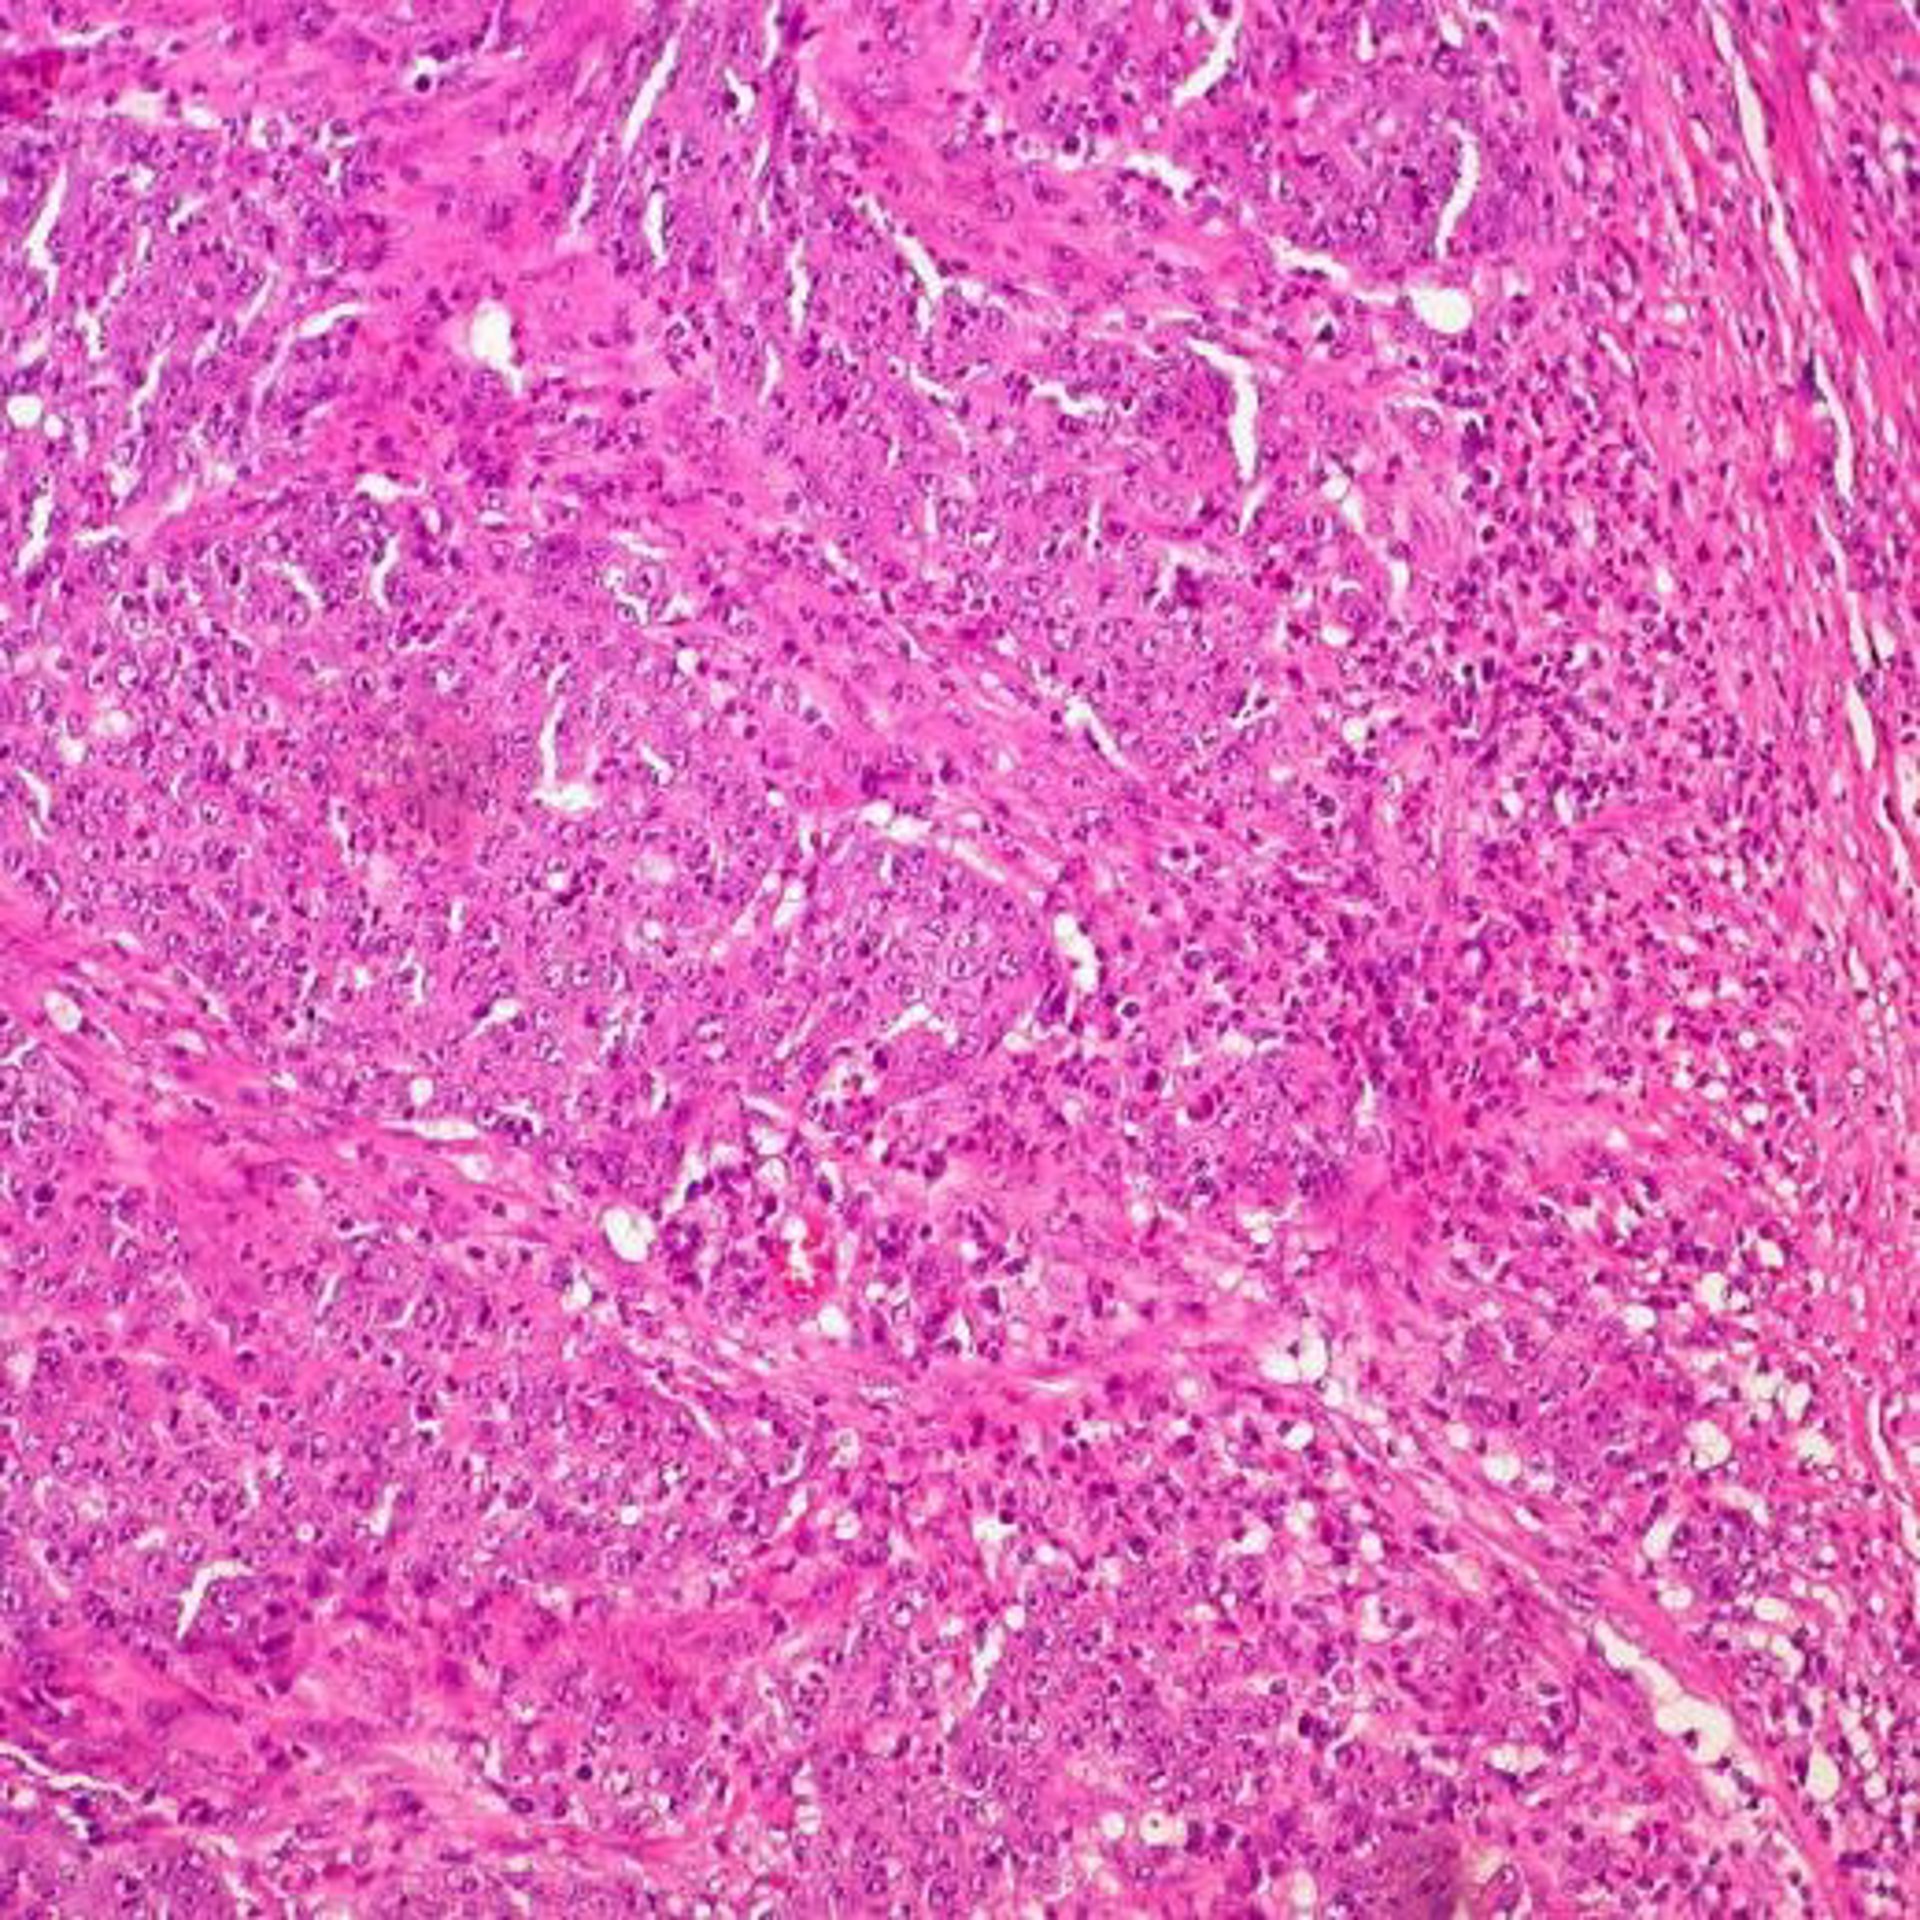

Cáncer de colon

Cáncer de colon - UCM - Archivo